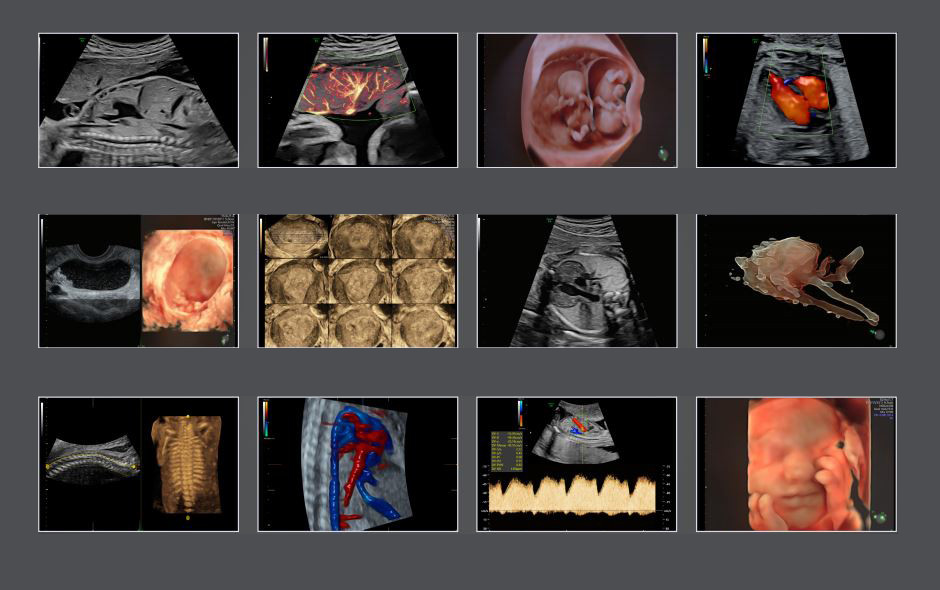

Thiết bị siêu âm 4D Voluson E8 là một trong những dòng máy siêu âm hiện đại nhất được sử dụng chủ yếu tại các bệnh viện lớn trên thế giới.

Công nghệ HDLive tích hợp trong dòng máy E8 cung cấp hình ảnh 4D có độ phân giải cao, biến động theo thời gian thực hỗ trợ đắc lực cho giải phẫu và theo dõi, đánh giá sự phát triển của thai nhi đặc biệt là phát hiện các dị tật phức tạp ngay từ giai đoạn sớm của thai kỳ.

Tính năng cải thiện hình ảnh cho phép quan sát chi tiết đến cả hệ thống tim mạch của thai nhi, tăng chất lượng kiểm tra tiếng vang, đánh giá các rối loạn nhịp tim và đo chức năng tim thai tốt hơn nhiều các dòng máy siêu âm thông thường.

|

| Hình ảnh siêu âm thai các tuần từ thiết bị Voluson E8 |